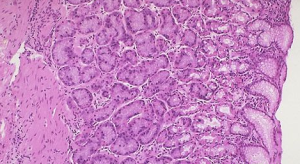

腸瘺病理圖2.結腸克羅恩病(Crohn’sdisease)結腸克羅恩病有腹痛、發熱、外周血白細胞升高、腹部壓痛、腹部包塊等表現,瘺管形成是其特徵,這些症狀、體徵與憩室炎相似。內鏡和X線檢查可發現鋪路石樣改變的黏膜,較深的潰瘍,病灶呈“跳躍”樣分布有助於鑑別。內鏡下黏膜活檢如發現非乾酪性肉芽腫則有診斷價值。.潰瘍性結腸炎可表現為發熱、腹痛、血便,外周血白細胞增多,結腸鏡下可見黏膜呈瀰漫性炎症、充血、水腫。隨病情發展,可出現糜爛、潰瘍、假性息肉,潰瘍之間殘存黏膜萎縮,晚期有腸腔變窄,結腸袋消失等表現。病檢可見杯狀細胞減少及隱窩膿腫等改變。缺血性結腸炎缺血性結腸炎好發於老年人,可與結腸憩室病同時發生。臨床表現多為劇烈腹痛後解黑大便。鋇劑灌腸檢查見到特徵性的拇指紋徵象可診斷缺血性結腸炎。結腸鏡檢有助於診斷本病。